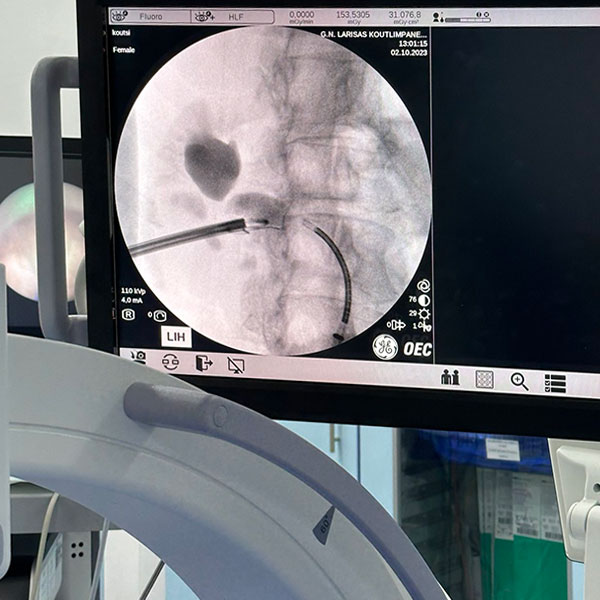

- Εύκαμπτη laser νεφρολιθοτριψία

- Εύκαμπτη laser ουρητηρολιθοτριψία

Επίσης, παρέχει διαδερμική νεφρολιθοτριψία με laser, ουρητηροσκοπική λιθοτριψία με laser, υπερηχοτομογραφικό έλεγχο, εύκαμπτη κυστεοσκόπηση, διορθική βιοψία προστάτη και αναλαμβάνει όλες τις μικροεπεμβάσεις, καθώς επίσης και την αντιμετώπιση της ακράτειας ούρων και τον ουροδυναμικό έλεγχο.